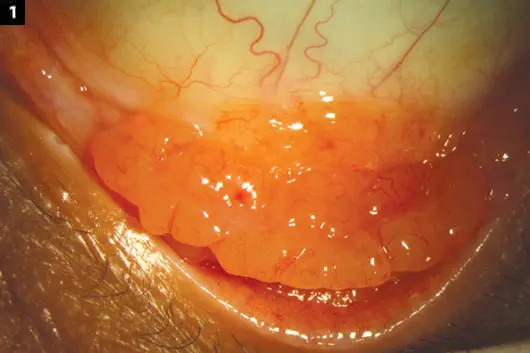

결막 림프종은 전신적인 림프육종, 림프구백형병, 호지킨 림프종과같은 전신 질환과 관련해서 눈에 나타나기도하며,

전신질환과 무관하게 눈에만 나타나기도합니다.

보통 처음결막에서 결막림프종이 진단되는 경우의 20% 에서 전신 침범이 발견됩니다.

따라서 처음 진단되면 전신평가를 위한 검사라 필요합니다.

대부분 면역조직 화학 검사에서 B cell lymphoma가 대부분입니다.